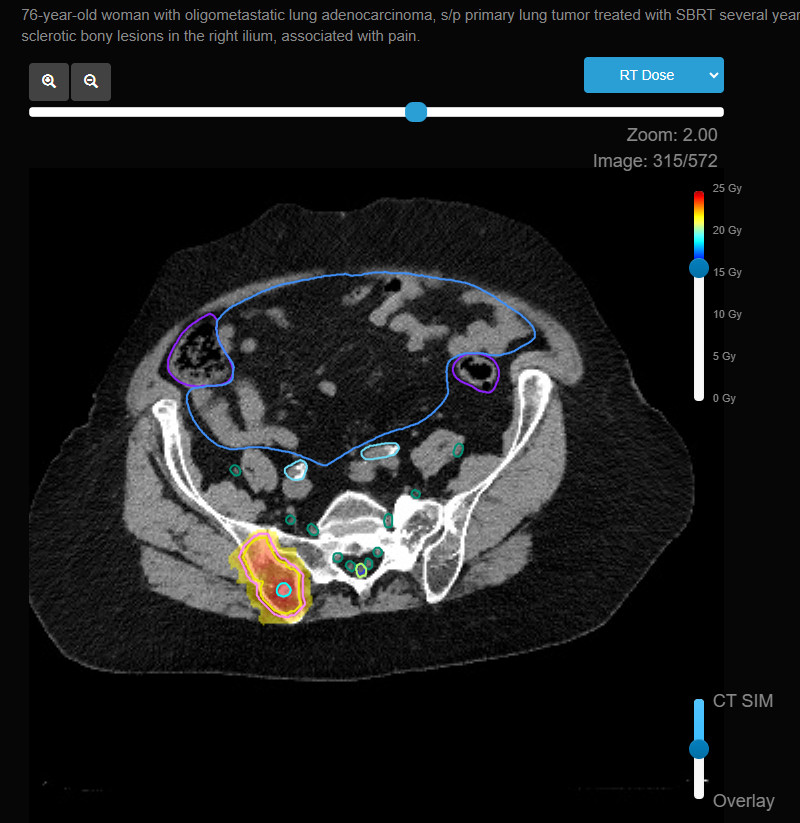

- Stereotactic Body Radiation Therapy (SBRT): SBRT delivers high doses of radiation with precision and is sometimes used for oligometastatic disease or when a high dose is needed in a small, focused area, such as a spinal metastasis.

- Weight-Bearing Bones: In cases of metastasis to weight-bearing bones, such as the femur or pelvis, the entire affected bone or the critical areas (e.g., femoral neck, acetabulum) are included in the radiation field to reduce the risk of fractures.